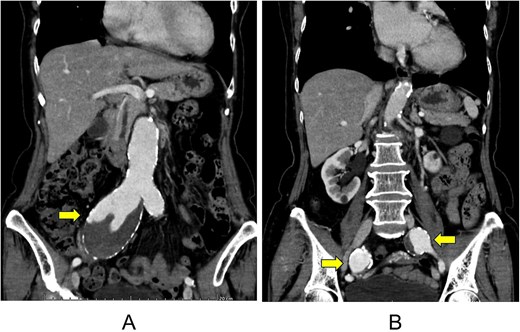

A 75-year-old female presented to her primary care physician with complaints of a left inguinal mass and palpitations that had persisted for several months. Her medical history included hypertension, dyslipidaemia, and Mycobacterium avium complex pulmonary disease (MAC-PD). Computed tomography (CT) revealed an abdominal aortic aneurysm with a maximal diameter of 42 mm, as well as aneurysms in the right (maximum diameter of 57 mm) and left (maximum diameter of 30 mm) common iliac arteries (Fig. 1). In cases of bilateral common iliac artery aneurysms associated with an abdominal aortic aneurysm, management typically involves aorto-bilateral iliac or femoral artery grafting. Thus, open surgical repair was planned. Prior to repair of the aortic and iliac aneurysms, the patient underwent risk stratification and preoperative cardiac evaluation to minimize perioperative cardiac and pulmonary complications.

Computed tomography images of an abdominal aortic aneurysm (A) and multiple aneurysms of the right and left common iliac arteries (B).